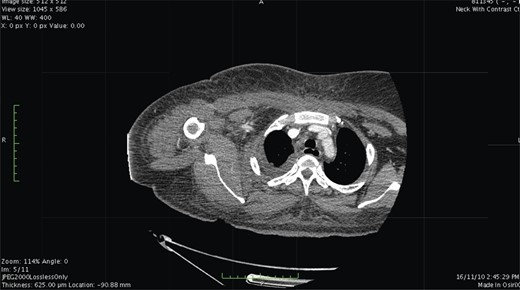

Contrast-enhanced computed tomography (CT) scan showed extensive cellulitis and thrombosis of the internal jugular vein and marked necrosis of the underlying muscles (Figs 1 and 2). The basic investigations revealed a haemoglobin level of 7.5 g/dl, a random plasma glucose level of 227 mg/dl and the fasting glucose level was 240 mg/dl.

Contrast-enhanced CT. At level of the mediastinum shows extensive inflammation involving the fat and the muscles on the right side.